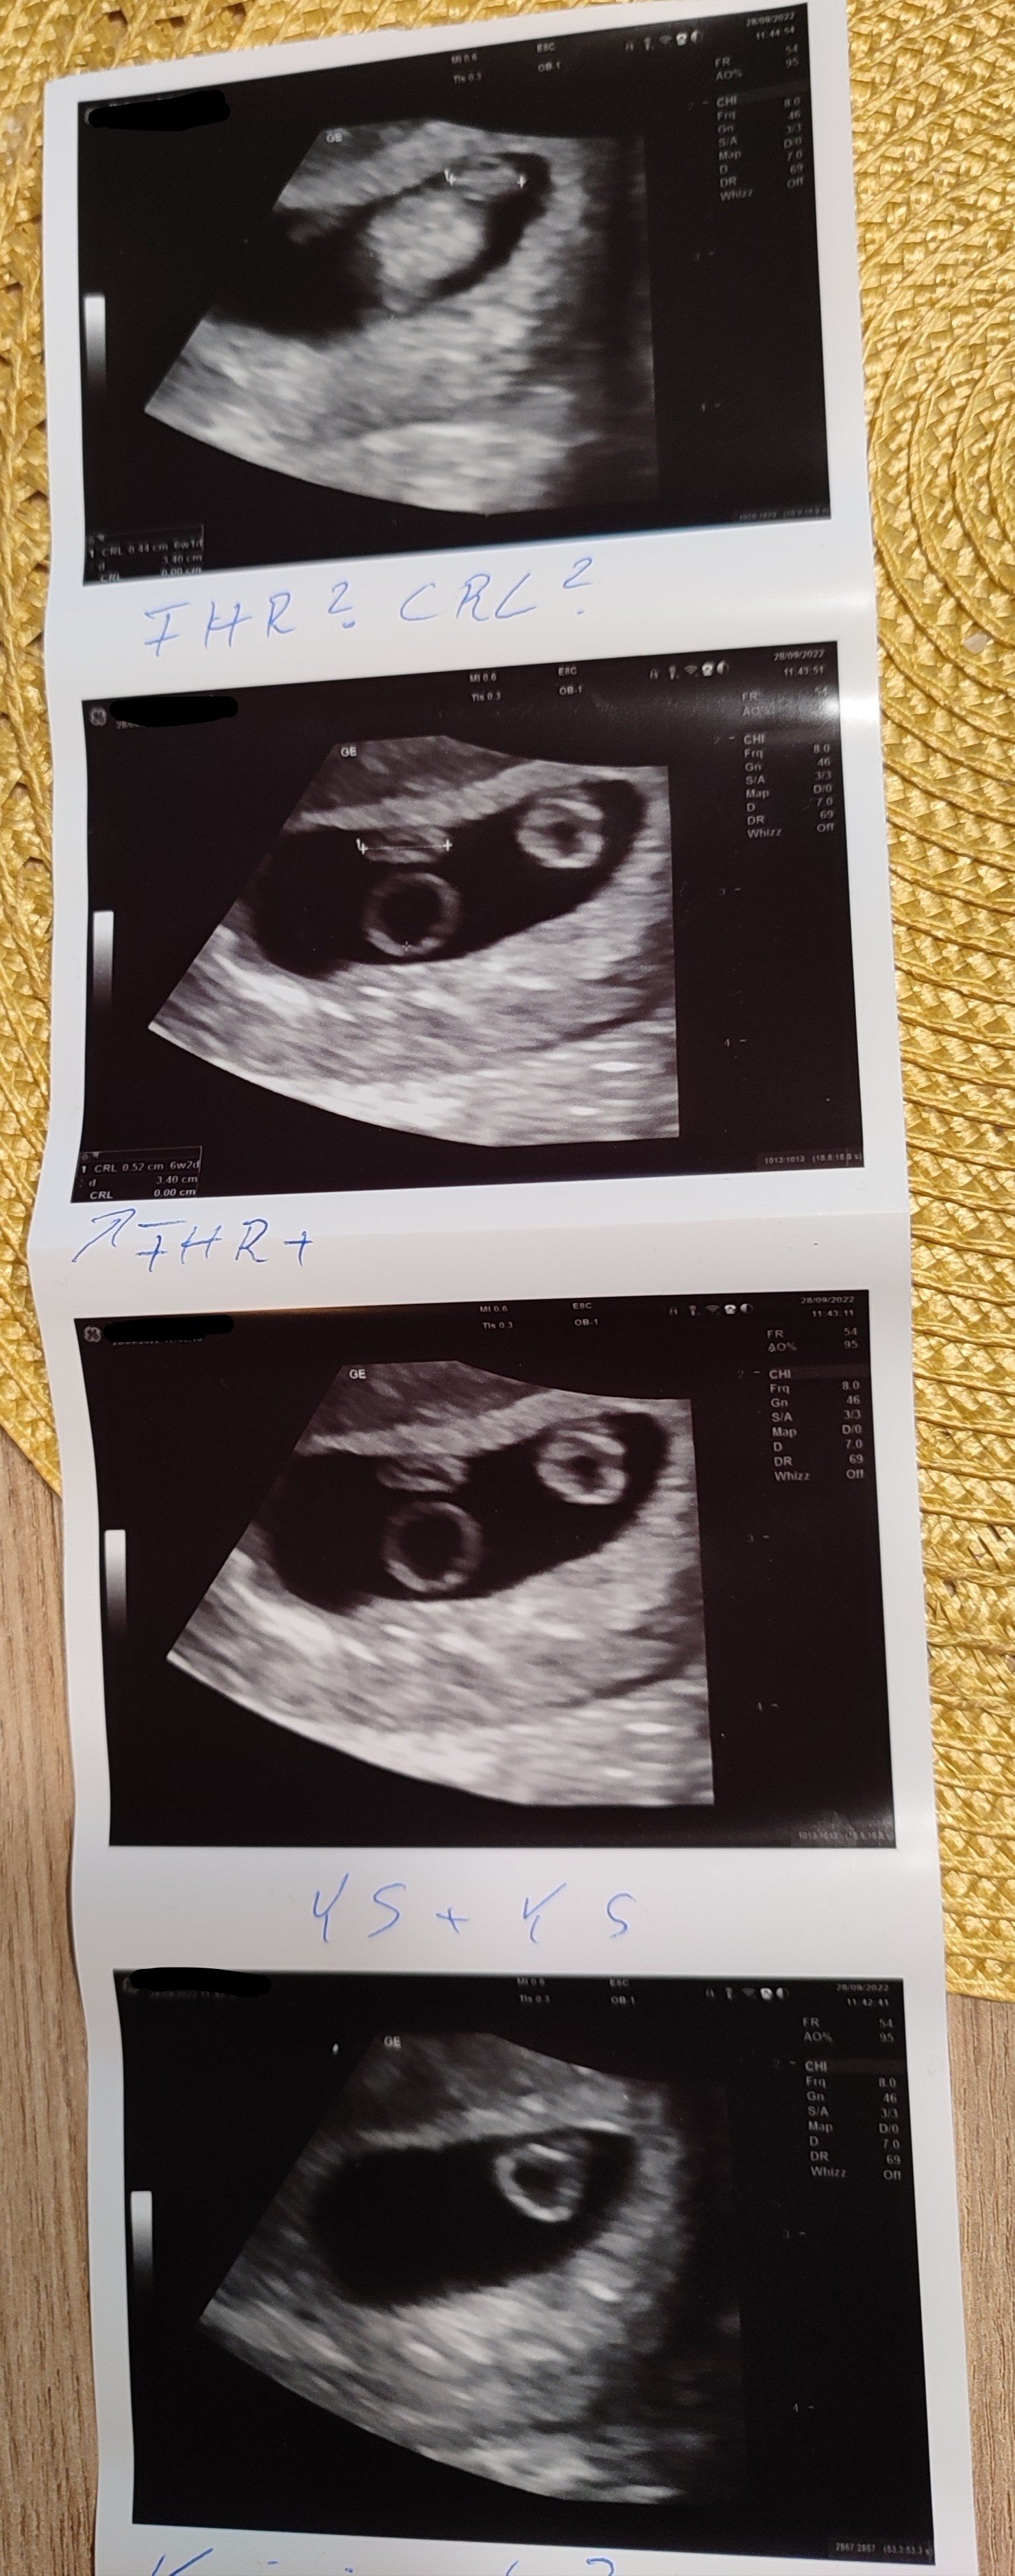

Jestem i ja po drugiej wizycie (w pierwszej tydzień temu było za wcześnie na serduszko- wtedy 5+3) a dziś...

Mamy jedno ❤️ i podejrzenie drugiego jegomościa 😳

Lekarz wpisał podejrzenie ciąży bliźniaczej oraz rekomendował spokojne podejście do tematu, bo może się wszystko wydarzyć, że np. jeden zarodek zostanie wchłonięty itp.😨

Mam wizytę kontrolną za tydzień zobaczyć czy u drugiego bije serduszko i jak to się rozwija.